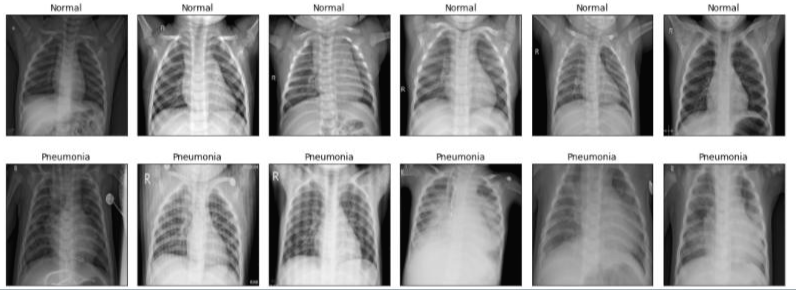

X-ray 사진을 이용한 폐렴 진단

- 소아 환자들의 x-ray 데이터를 보고 정상과 폐렴을 분류하는 것이다.

- ResNet50V2를 이용해서 이미지를 분류하였고, sequential 모델을 사용하여 층을 쌓았다.

- 데이터가 1GB가 넘었기 때문에 training만 1시간이 걸렸다.

- 정확도는 97%정도가 나왔다.